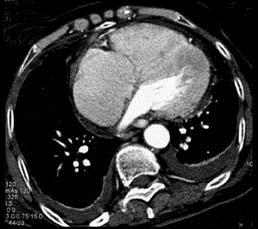

问题 男,38岁,反复咳嗽、咳痰伴发热15年余,痰结核菌素试验(—),结合CT图像,最可能的诊断是 ( )

选项 A.肺癌 B.肺结核 C.肺结节病 D.肺转移瘤 E.肺淀粉样变性

答案 E